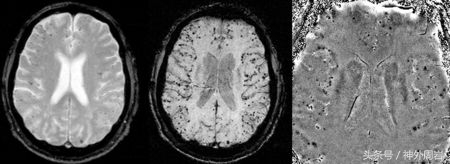

此外,引起脑出血的还有另外一个原因—— 血管淀粉样变 。这个名词好陌生啊,仿佛是个食材。这个名称的由来就是淀粉样物质沉积于大脑皮质及软脑膜中小血管壁。这种病占脑出血病因的10%-15%。这种病的主要特点就是脑叶出血,具有反复发作性,发病年龄通常在60岁以上。